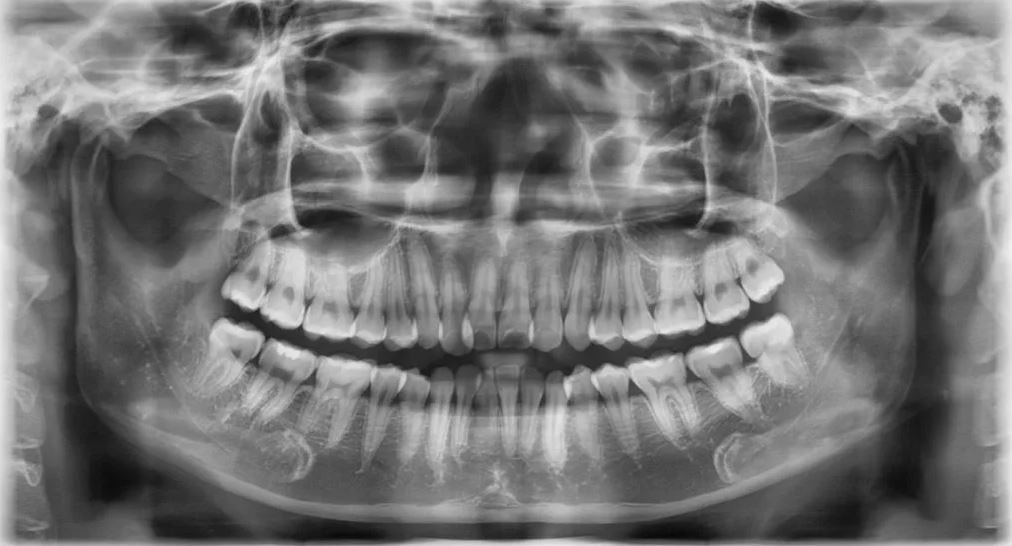

Để thực hiện niềng răng các bác sĩ phải lên phác đồ điều trị cụ thể đối với từng trường hợp. Để có thể chẩn đoán chính xác và lên kế hoạch điều trị hợp lý, bác sĩ phải hiểu rõ đặc điểm xương hàm, trục răng, mức độ lệch lạc của răng và độ cứng chắc của răng như thế nào... Do vậy chụp Xquang trước kh niềng rang là việc rất cần thiết. Thông qua những hình ảnh thu được từ việc chụp phim Xquang khi niềng răng kết hợp với hình ảnh thăm khám khoang miệng, ngoài mặt, lấy dấu mẫu hàm, bác sĩ mới có thể đưa ra được những nhận định và phán đoán chính xác về tình trạng răng, hướng dịch chuyển của răng sau khi niềng và lên phác đồ cụ thể cho từng trường hợp.

Niềng răng trong chỉnh nha là một điều trị trong khoảng thời gian dài, từ 2 - 3 năm, điều này có thể khiến bác sĩ không thể nhớ hết được những điều trị của mình cũng có thể bệnh nhân sẽ quên đi hàm răng trước khi niềng của bản thân. Vì vậy việc chụp Xquang sẽ cho phép bác sĩ và bệnh nhân có cái nhìn toàn diện và chính xác hơn trong quá trình niềng răng.

Bên cạnh đó, chụp phim Xquang là một trong những cách lưu trữ thông tin về tình trạng răng và xương hàm của bệnh nhân, dựa vào các hình ảnh trên phim qua các lần chụp bác sĩ và bệnh nhân có thể thấy được sự di chuyển của răng cũng như hiệu quả quá trình điều trị chỉnh nha.